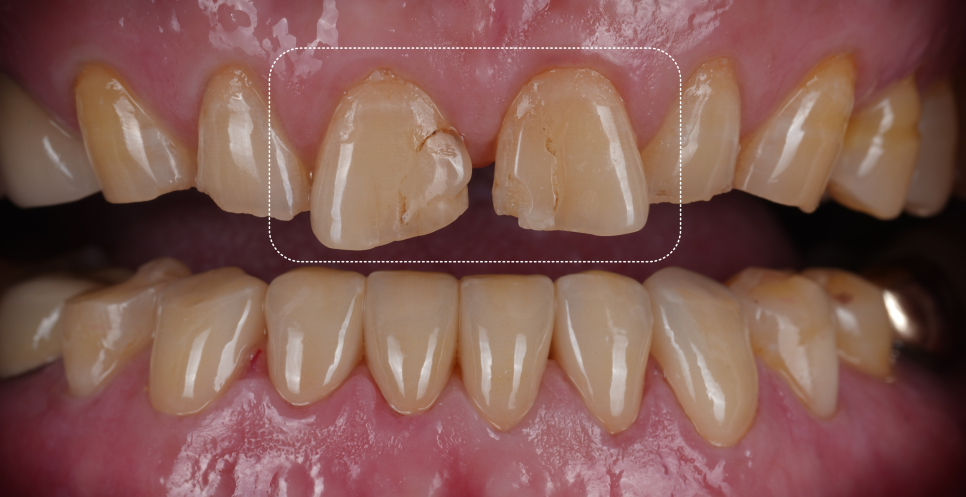

깊게 물리는 교합으로 이미 많이 닳아버린 앞니들

촬영일 : 251013

또, 아랫니가 많이 닳아있어 깊게 무는 형태인 'Deep bite(딥바이트)' 라고 부르는 과개교합 상태였죠.

오랜 시간 서로 부딪히며 위아래가 서로를 갈아버린 흔적이죠.

양쪽 작은 어금니 쪽에는 잇몸 가까이 패인 마모 부위도 있었고 찬물이나 칫솔질 때 "시큰시큰하다"라고 하셨어요.

환자분은 “아래 앞니가 많이 닳았어요"라고 말씀하셨지만 실제로는 아래 앞니에만 문제가 있는 것이 아니라 전체적인 교합, 마모 패턴을 같이 봐야 하는 상황이었어요.